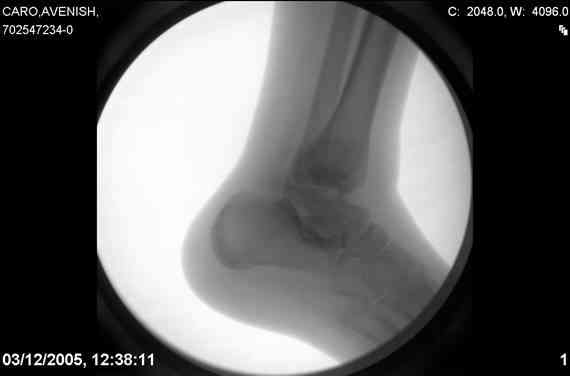

Re: Осколчатый перелом таранной кости

ya by popytalsya sobrat talus anatomichno,seichas pozdno operirovat iz za oteka,po etomy distrakziya apparatom budet optmalna.Posyalu vam podobyai moi sluchai.

14 years old girl

Fall from height ( 3rd floor)